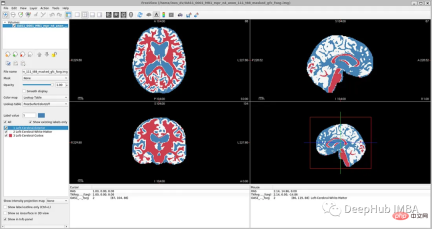

为了简化本教程,我们将使用以下标签,比OASIS-1但是要比FreeSurfer的少:

- Label 0: Background

- Label 1: LeftCerebralExterior

- Label 2: LeftWhiteMatter

- Label 3: LeftCerebralCortex

结果分析

最后我们要看看模型是如何推广到未知数据的这个模型预测的几乎所有东西都是左脑白质,一些像素是左脑皮层。尽管它的预测似乎是正确的,但仍有很大的改进空间,因为我们的模型太小了,可以选择更深的模型获得更好的效果。